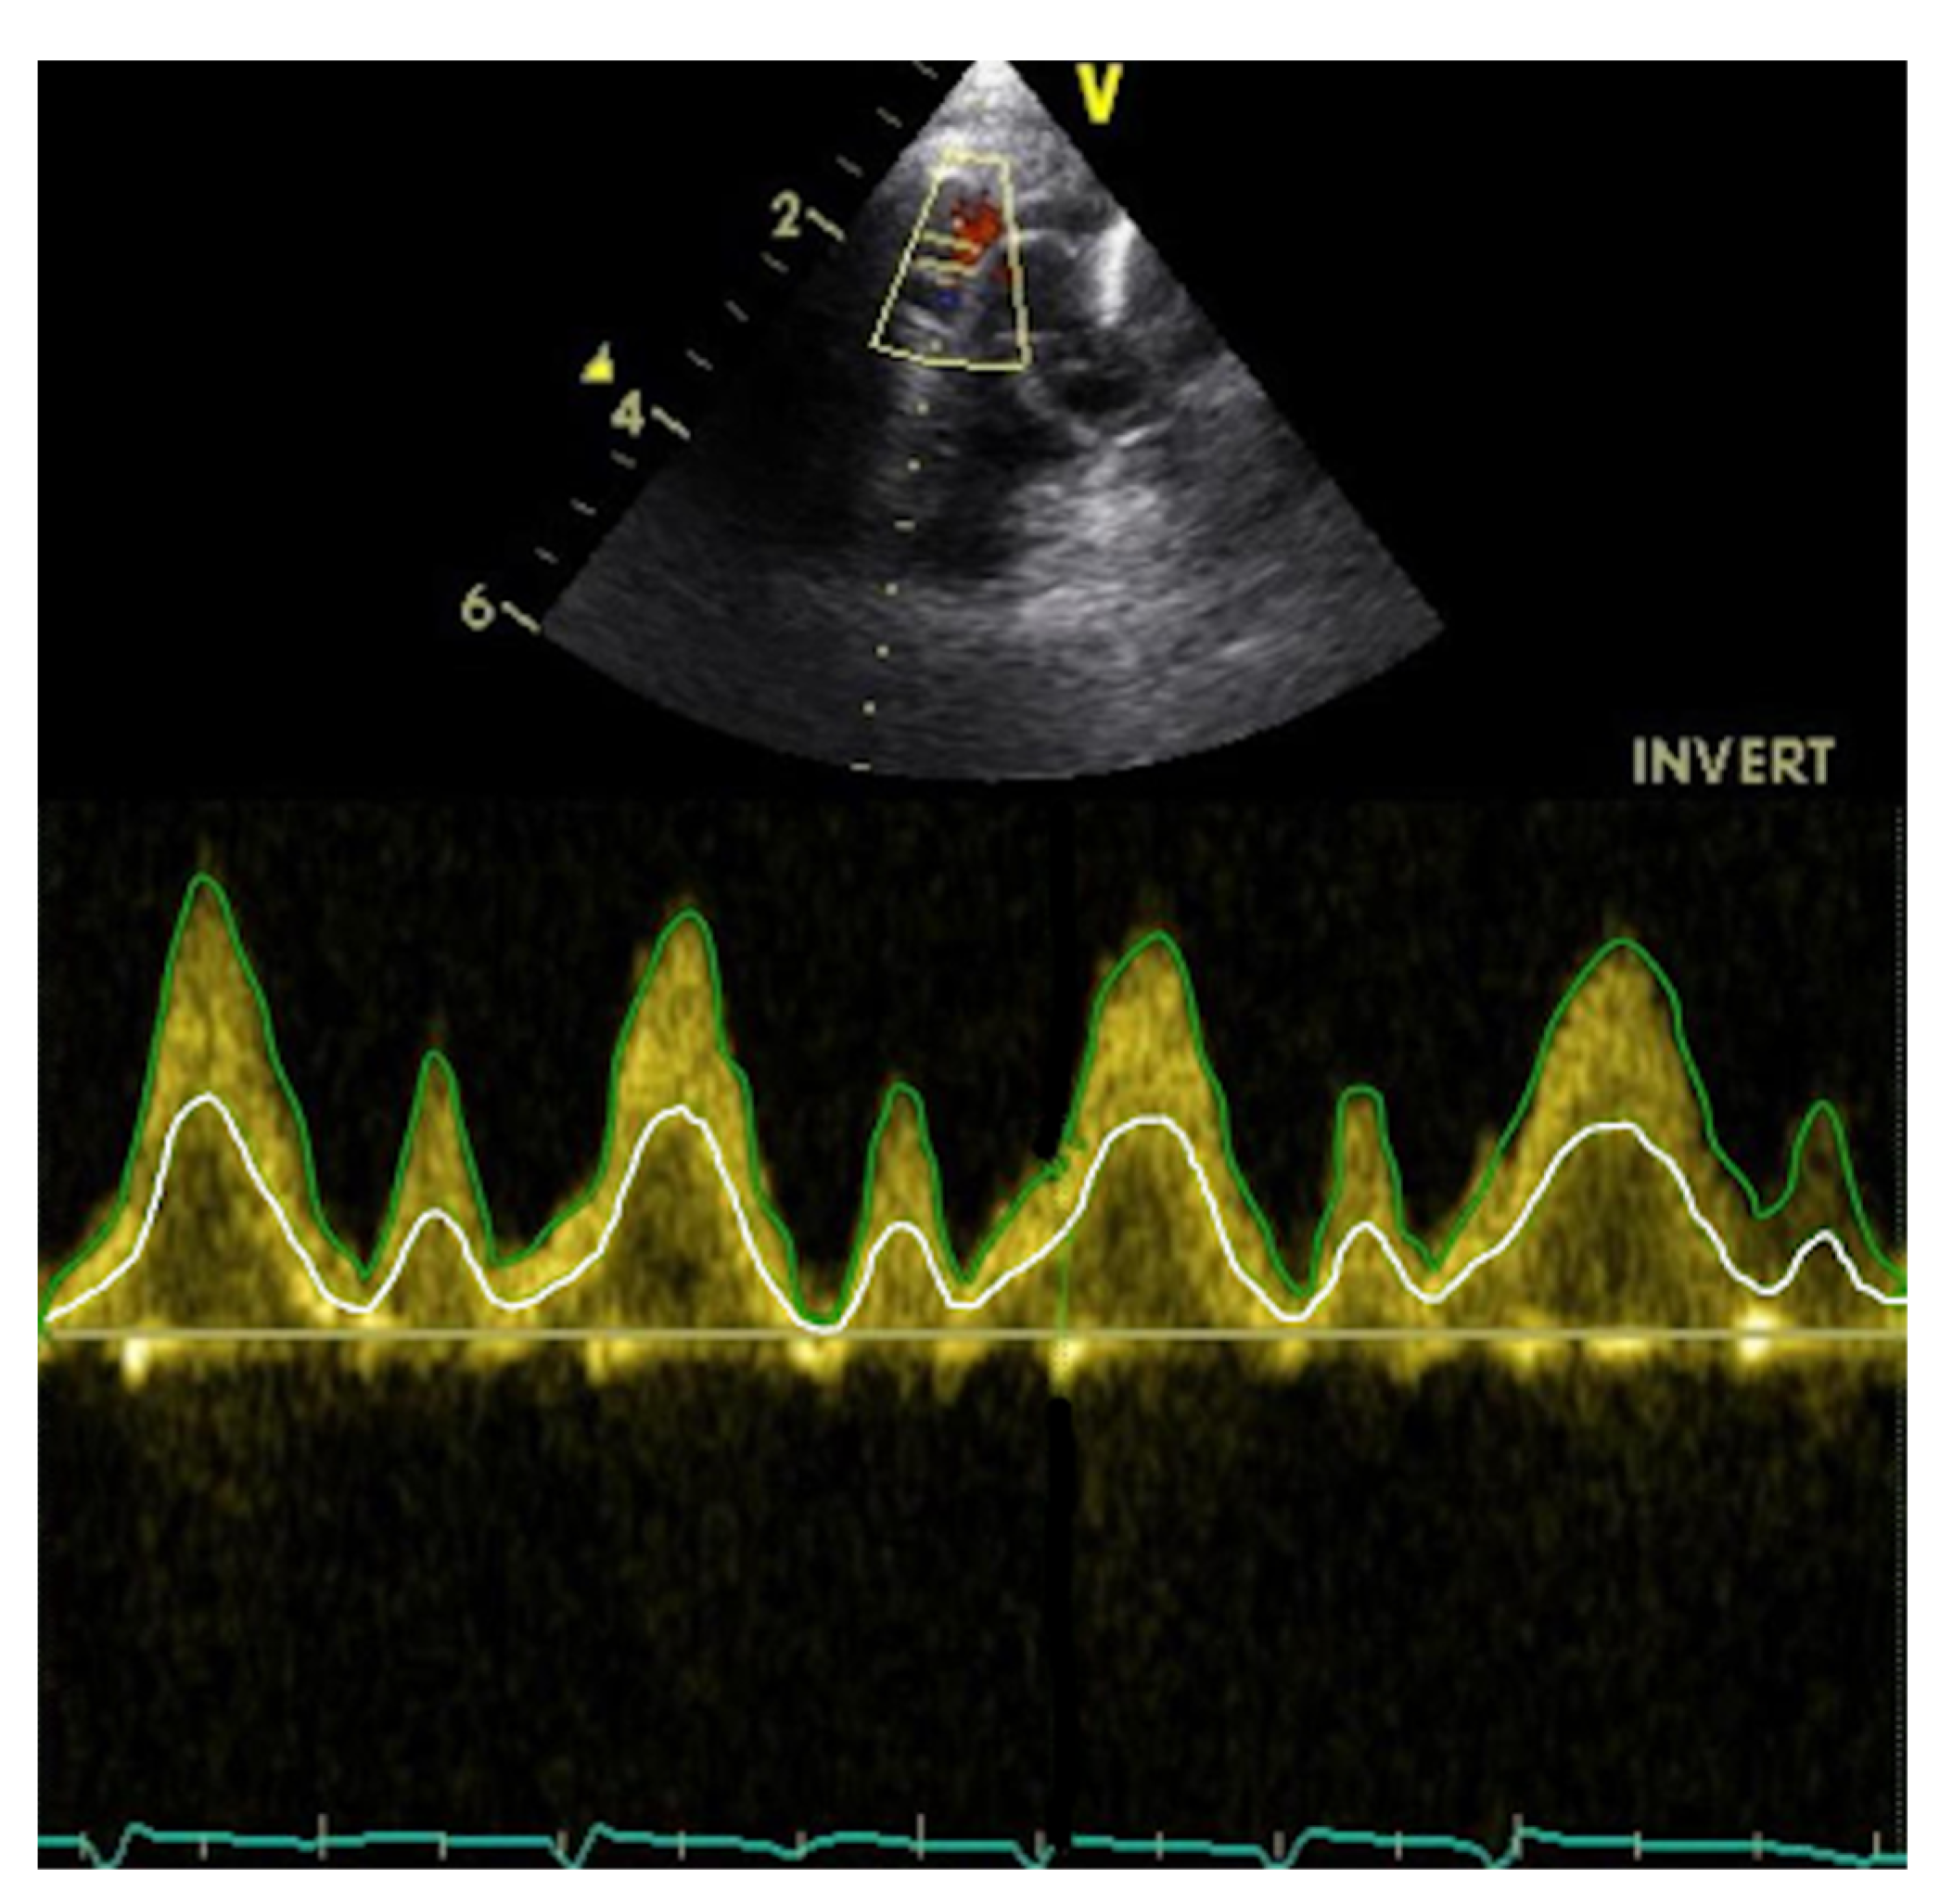

2.2.3. Method 3—Modified Superior Vena Cava Flow Technique

3.3. Method 3

| Method 3 | ||||

| SVC flow | −8 mL/kg/min | −25/+8 mL/kg/min | 13% | 7% |

| Area | −2.7 mm2 | −10/+4.8 mm2 | 35% | 17% |

| Suprasternal VTI | 0.5 cm | −1/+2.1 cm | 23% | 11% |